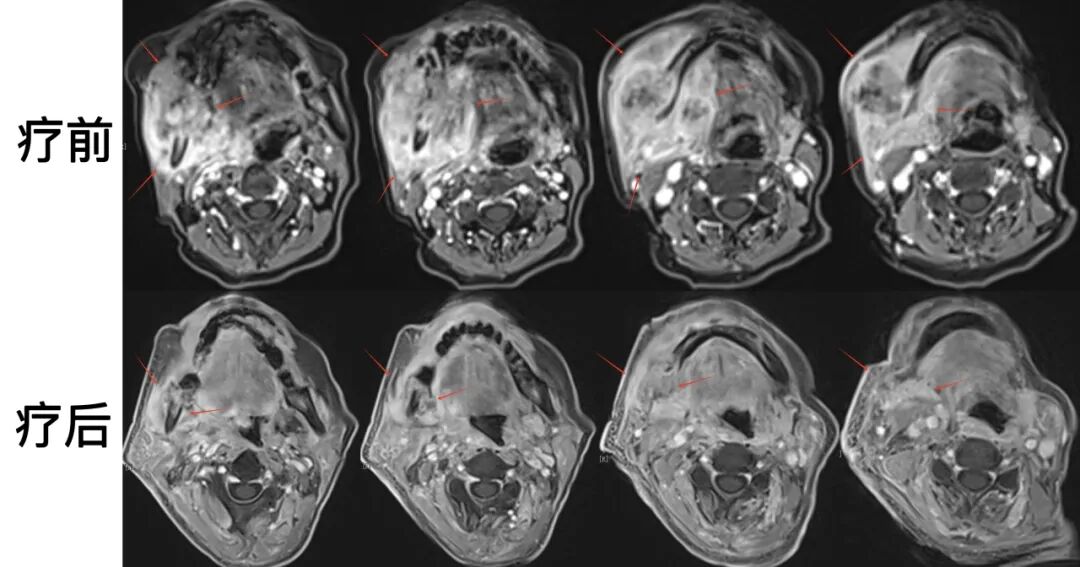

圖注:治療前后對比??谇活i部MR可見治療前累及范圍大;放療后復查可見,右側(cè)下頜骨骨質(zhì)破壞,伴軟組織腫塊形成,較前明顯縮小。